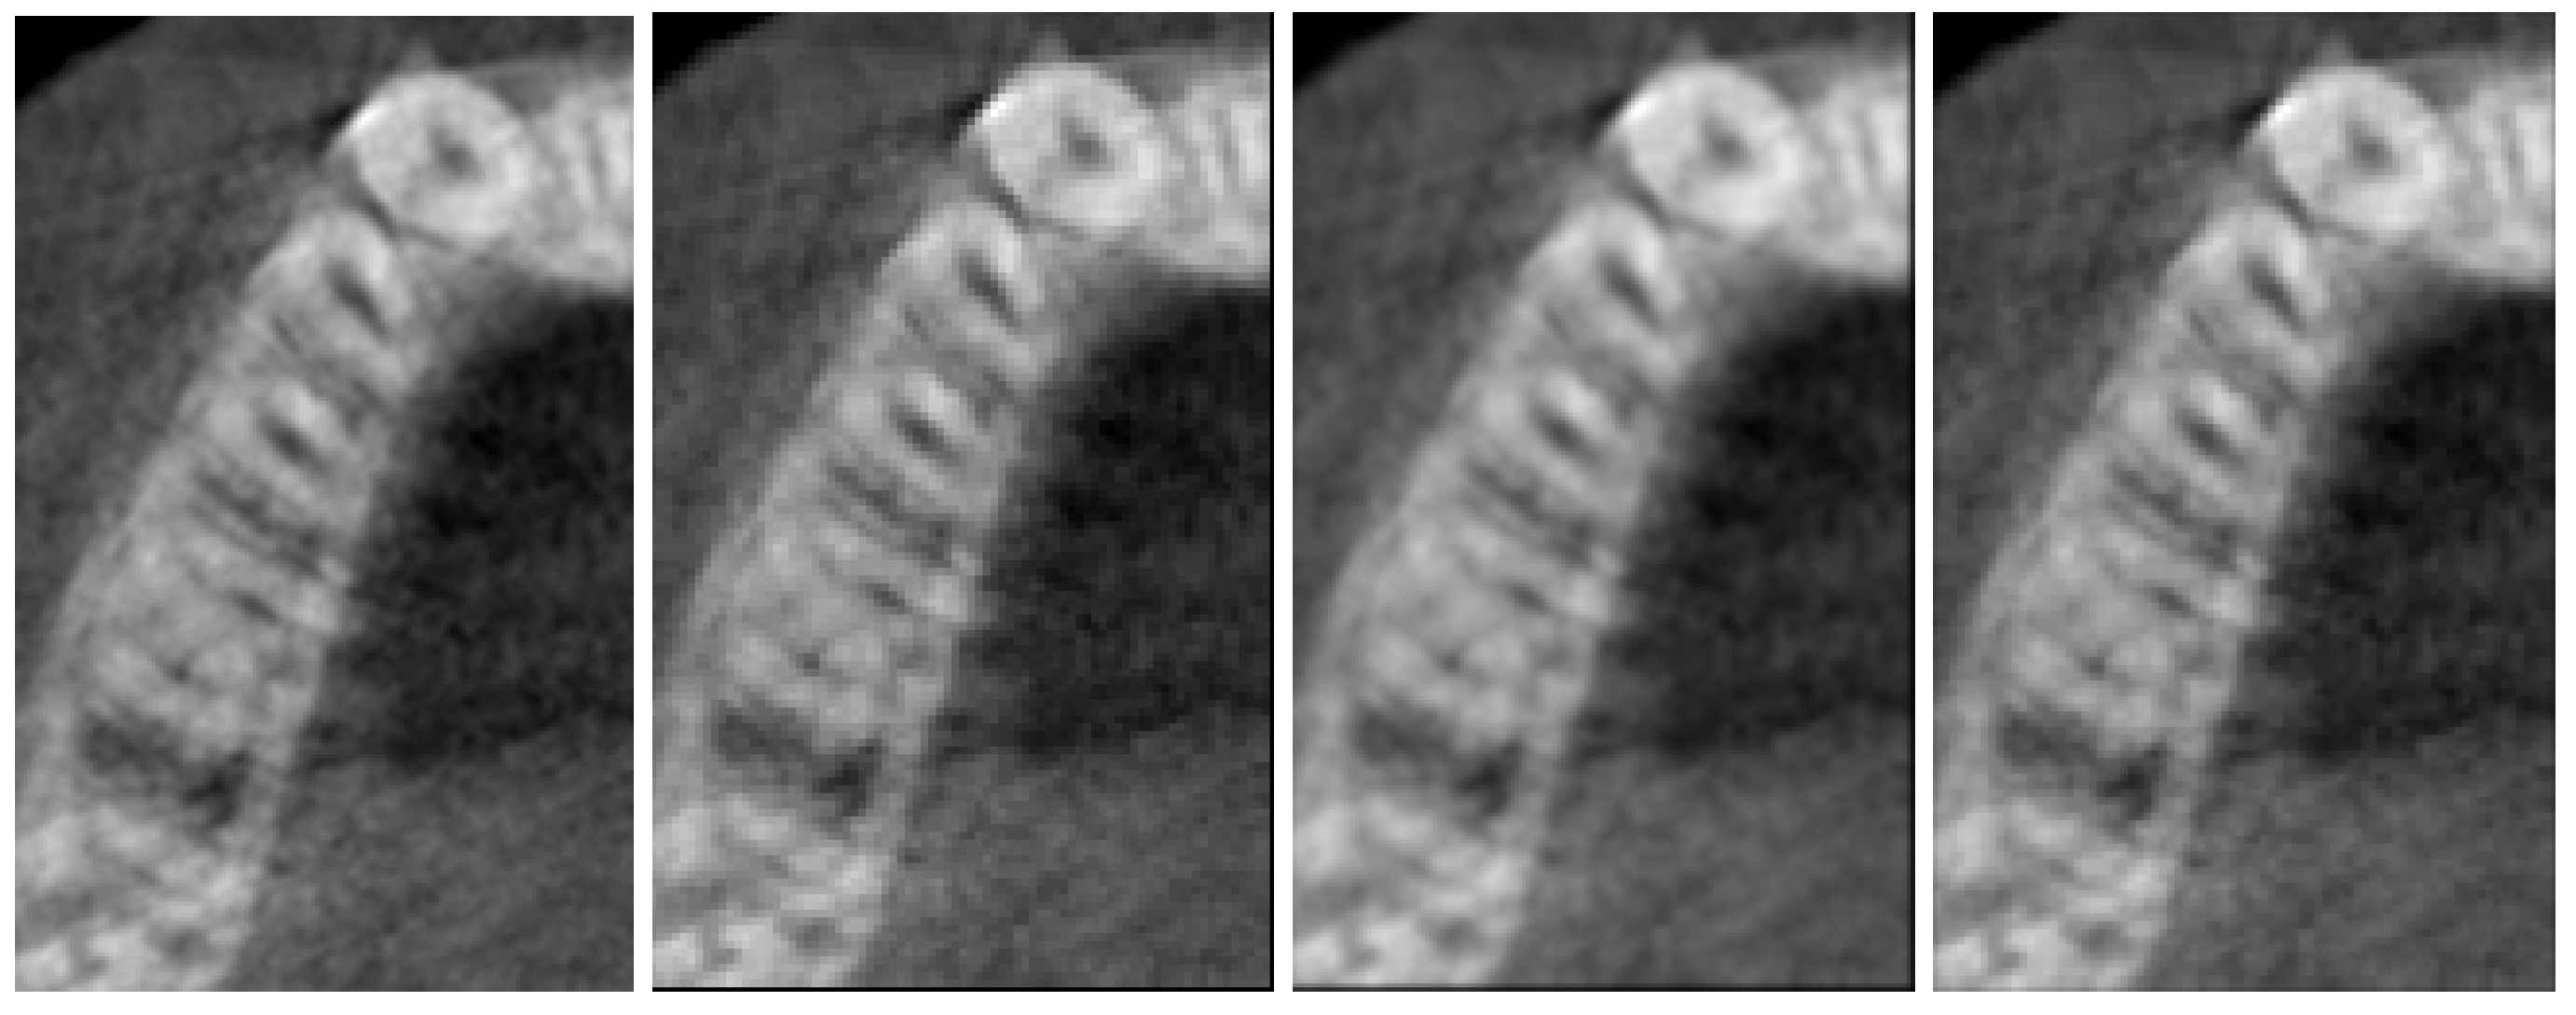

3. Numerical Results